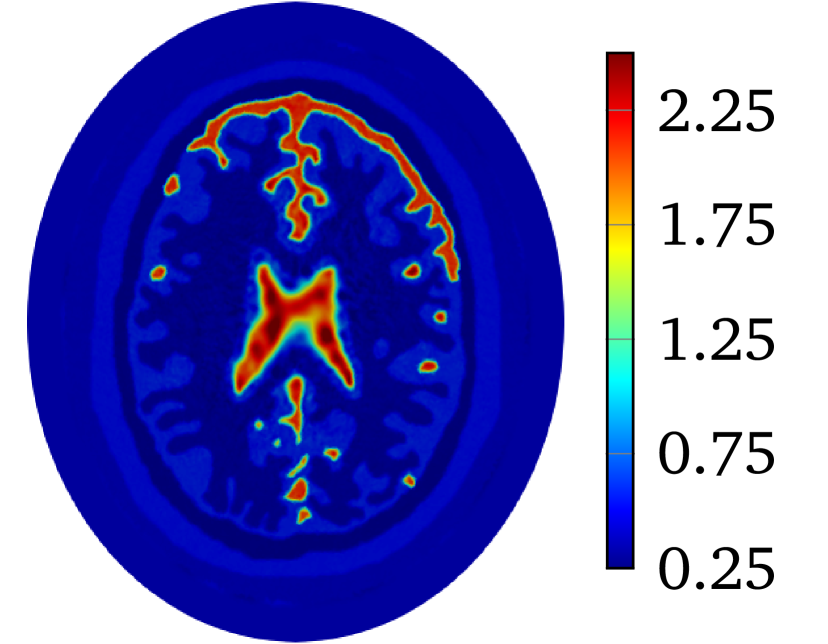

to produce with for 2D problem. The constant is selected so that . The value of is and for heart-lung model and human-brain model, respectively. The true smoothed distributions of for the two models are shown in Figure 2.

Though LM-SCEM performs well for reconstructing the conductivity map, its efficiency of the computation decreases quickly with the increase of measurements. Since EIT is not very sensitive to the change of interior conductivity, the electrical potential should converge faster than the convergence of the conductivity. The human-brain model is used here for numerical experiments with LM-SCEM. The elliptic domain is characterized with major and minor axes, and the domain is meshed with 36893 triangular elements. The parameters are given as , and . The current patterns and are used in the reconstruction. With noise, the iteration is terminated when or the maximum number of iterations equals 30. The reconstruction based on LM-SCEM is shown in Figure 7(a). of each current pattern is computed with SCEM and for -th iteration, easily follows then. The variation of the relative error and are shown in Figure 6(a) and Figure 6(b), respectively. As can be seen, slowly converges to . This error is much larger than the input noise level, this is mainly caused by the complexity of the phantom and the high contrast of among different tissues. But the potentials on the boundary for both and converge fast to a level of in few iterations. Therefore, the boundary potential converges much faster. This property is exploited here to accelerate the computation by mixing LM-SCEM and LM-DCM, as demonstrated in Algorithm 2. In this computation, the LM-SCEM is stoped when for all current patterns are smaller than . The LM-DCM is performed in the region with . The potential on is computed with SCEM and the reconstructed from LM-SCEM. The power density in can be reconstructed with the method introduced by Ammari et al [4]. However, it requires the knowledge on the deformation caused by the ultrasonic waves, therefore, we compute it with DCM instead. Noise with SNR is added, and LM-DCM is used for the reconstruction. The relative error is given in Figure 6(a). The conductivity map is reconstructed with in 30 iterations, and the result is given in Figure 7(b). Here, the time required for 30 LM-DCM iterations is about 20 minutes which is approximately the time needed for one LM-SCEM iteration. So the reconstruction efficiency is greatly improved, and better results are obtained. A similar computation with noise is further considered here. As seen in Figure 6(b), increasing noise does not influence much the convergence of the boundary potential, therefore, this mixed approach can be a good way to remove noise from the measured power density. With 40dB noise in the reconstructed power density in , the distribution of obtained with LM-DCM is shown in Figure 7(d). Comparing it to the results obtained with LM-SCEM, as shown in Figure 7(c), a better noise tolerance is observed in LM-DCM.